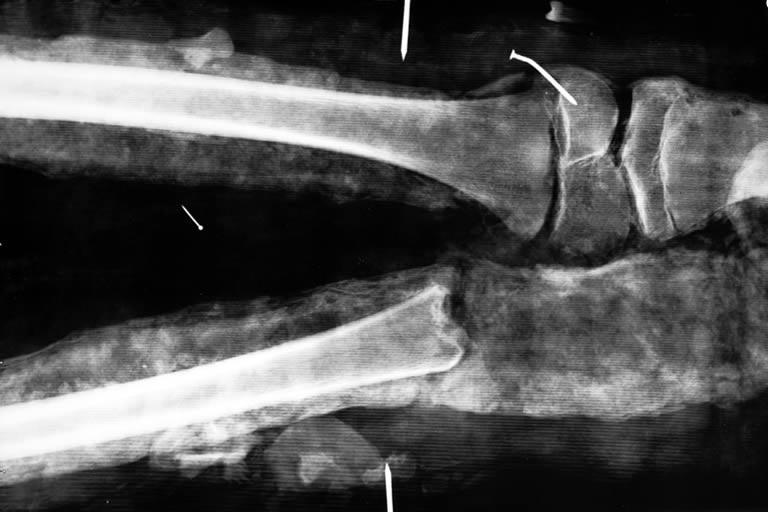

Una radiografia della sua parete addominale ha rilevato la presenza di un particolare parassita, un maschio di Dracunculus medinensis, detto anche filaria di Medina o verme di Guinea. È probabilmente l’omicida di ‘1770’.

È probabile che sia quello che è successo a ‘1770’. I mummificatori hanno cercato di “riparare” il danno, con delle canne strette da un tessuto a simulare le gambe amputate fino a ricostruire uno dei due piedi, e ponendo nella fasciatura anche due sorte di pantofole colorate, un particolare commovente nella sua semplicità.